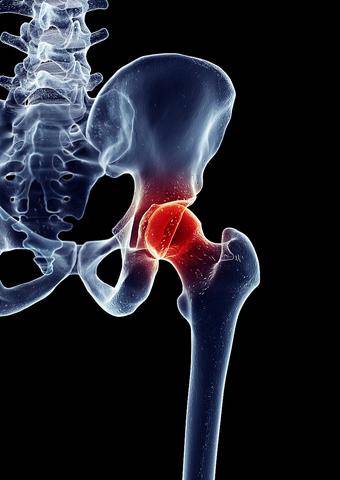

髋部反复出现的疼痛,往往是股骨头病变最直接的警示。当股骨头因缺血坏死、创伤或退行性改变发生损伤时,关节内炎症反应会刺激周围神经和滑膜组织,引发持续性的髋关节疼痛。这种疼痛初期可能只在活动后出现,随着病变进展,连休息时也会隐隐作痛。

很多人走路时突然发现腿脚不听使唤,甚至出现跛行或无力感,这往往与股骨头健康受损直接相关。股骨头作为髋关节的核心部分,负责连接大腿骨和骨盆,支撑身体重量并实现灵活运动。一旦它发生病变或损伤,比如因缺血坏死或长期磨损,就会破坏关节的稳定性。结果,下肢活动受限,走路时容易感到僵硬或失控。这种功能障碍如果不及时干预,可能逐渐加重行动障碍,影响日常行走。因此,识别股骨头问题的早期迹象至关重要。

当股骨头坏死发生时,血液供应中断导致骨头组织逐渐死亡。起初,可能只是轻微髋关节疼痛,尤其在走路或站立时明显。随着坏死区域扩大,骨头结构变弱,引发更严重的炎症和僵硬。这时,关节活动范围缩小,行走能力开始下降,出现不稳或跛行。如果不及时处理,骨头可能塌陷,关节严重变形,最终完全丧失行动自由。整个过程从轻微不适到严重功能障碍,一步步侵蚀日常活动。